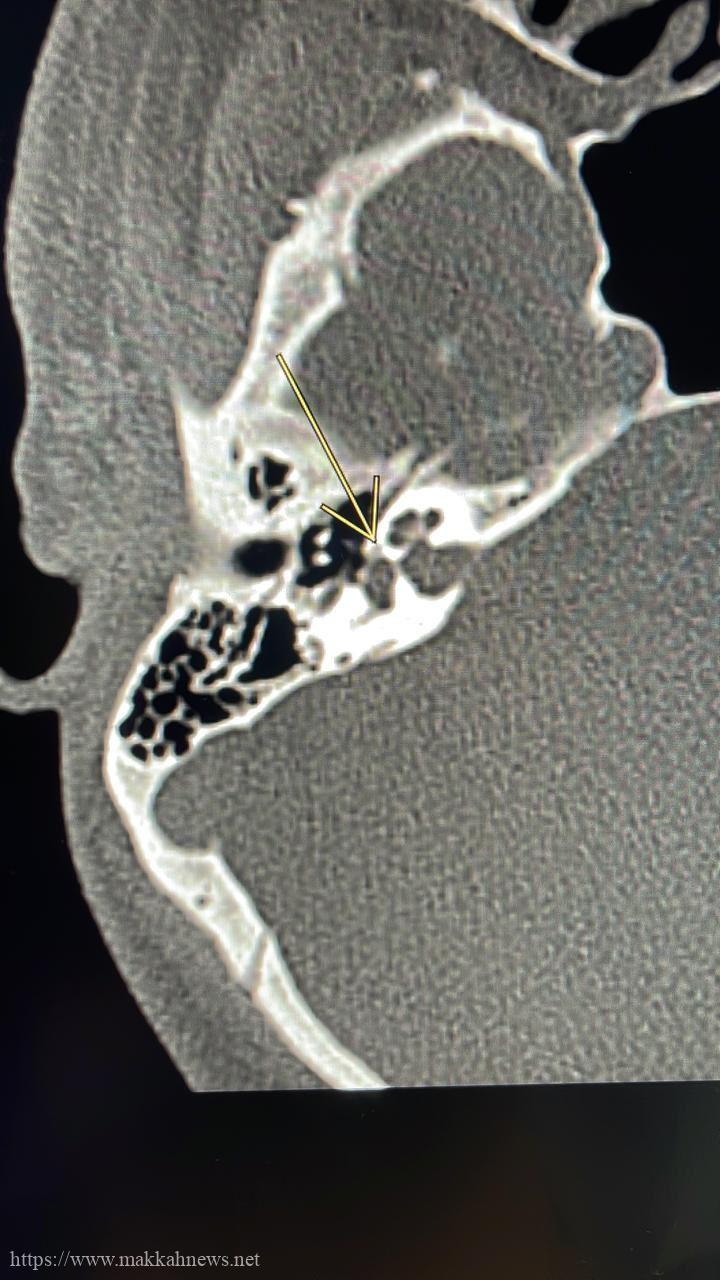

عملية مجهرية لثقب عظمة ركاب متصلبة و تركيب عظمة صناعية تحت التخدير الموضعي بطبية مكه تنهي معاناة ثلاثيني

نجح فريق طبي بمركز الرأس والعنق وقاع الجمجمة بمدينة الملك عبدالله الطبية بالعاصمة المقدسة عضو تجمع مكه المكرمة الصحي من…